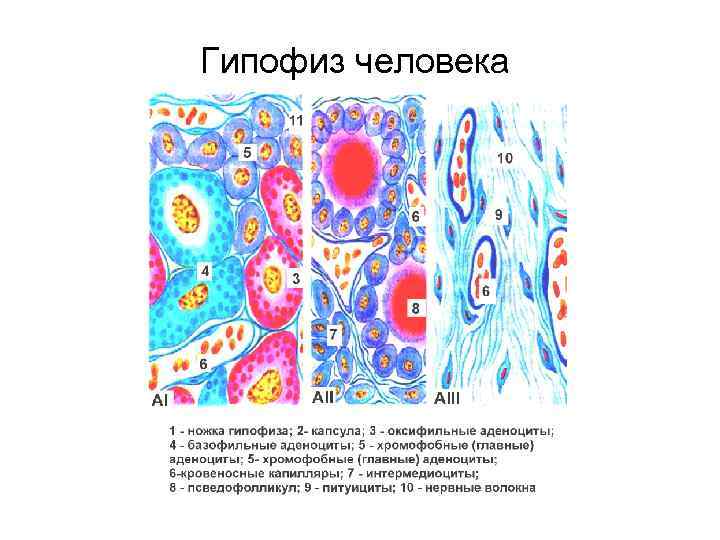

Гипофиз человека

Гипофиз человека

Гипофиз человека

Гипофиз человека